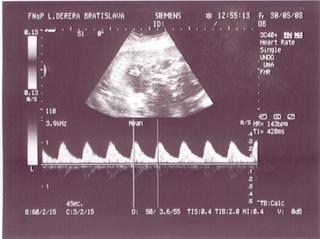

@bv_alexandra 3Dčko je skôr pre potešenie, morfologický UV je na diagnostiku, vidno na ňom orgány a kosti bábätka, vidno chlopne srdiečka, je možné zmerať dĺžku kostí a tak podobne, len pre porovnanie, už som to sem dávala aj predtým a písala som o tom, pridávam ti fotky z môjho prvého tehu, tie "farebné" sú z 3Dčka tam je krásne vidieť bábätko, tváričku, črty tváre, je vidieť na koho sa podobá, ako vyzerá, na morfologickom, to je ten čiernobiely vidieť bábo "zvnútra" aby sa potvrdilo že je úplne zdravé a nemá žiadne vývojové vady, podľa dĺžky kostí ti tam aj spresnia termín pôrodu.